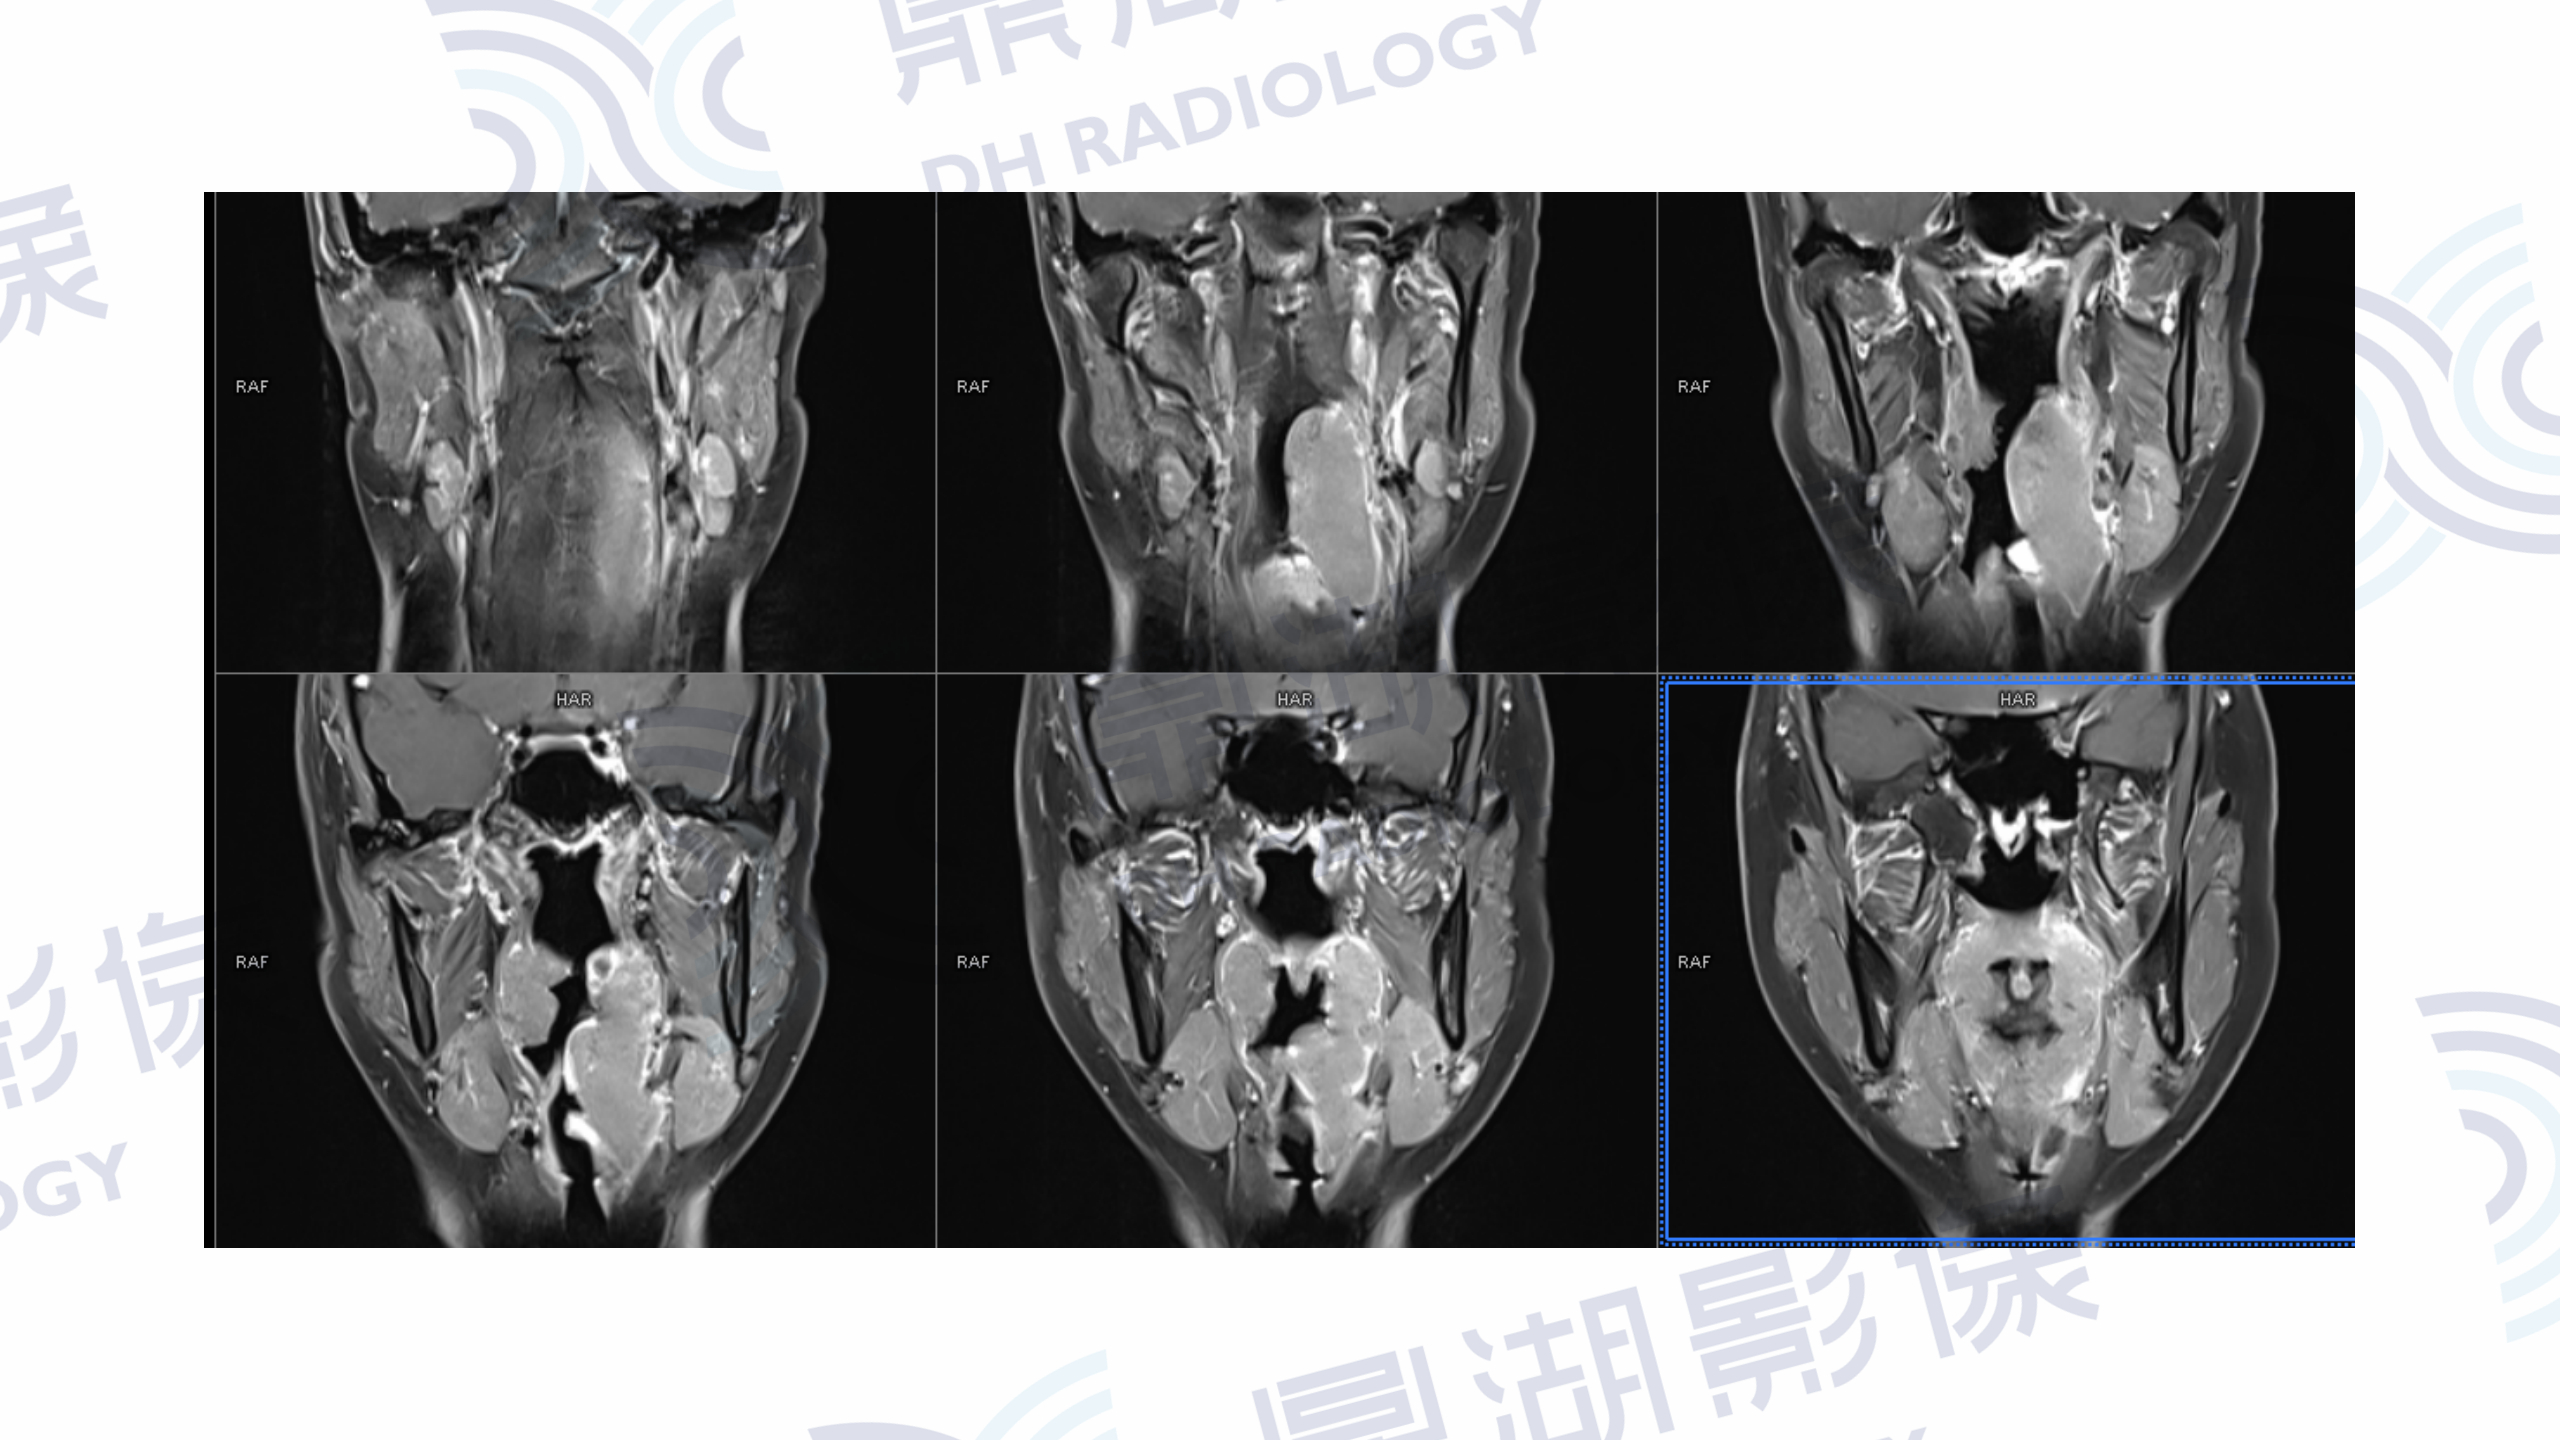

MR增强检查提示:口咽左侧壁至左侧声门上不规则软组织肿块,病灶突入咽腔,信号均匀,T1WI呈等信号,T2W呈稍高信号,DWI呈高信号,增强扫描呈轻度均匀强化,左侧杓状会厌皱襞水肿,左侧梨状窝消失。